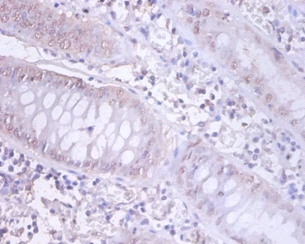

Immunohistochemical analysis of paraffin-embeded human colorectal carcinoma using #42405 at dilution of 1:100.

Immunohistochemical analysis of paraffin-embeded human prostate using #42405 at dilution of 1:100.